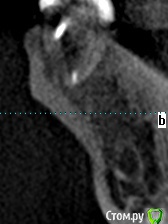

meld Опубликовано 7 ноября, 2017 Автор Поделиться Опубликовано 7 ноября, 2017 Прицельный снимок 38 зуба и его срезы Ссылка на комментарий